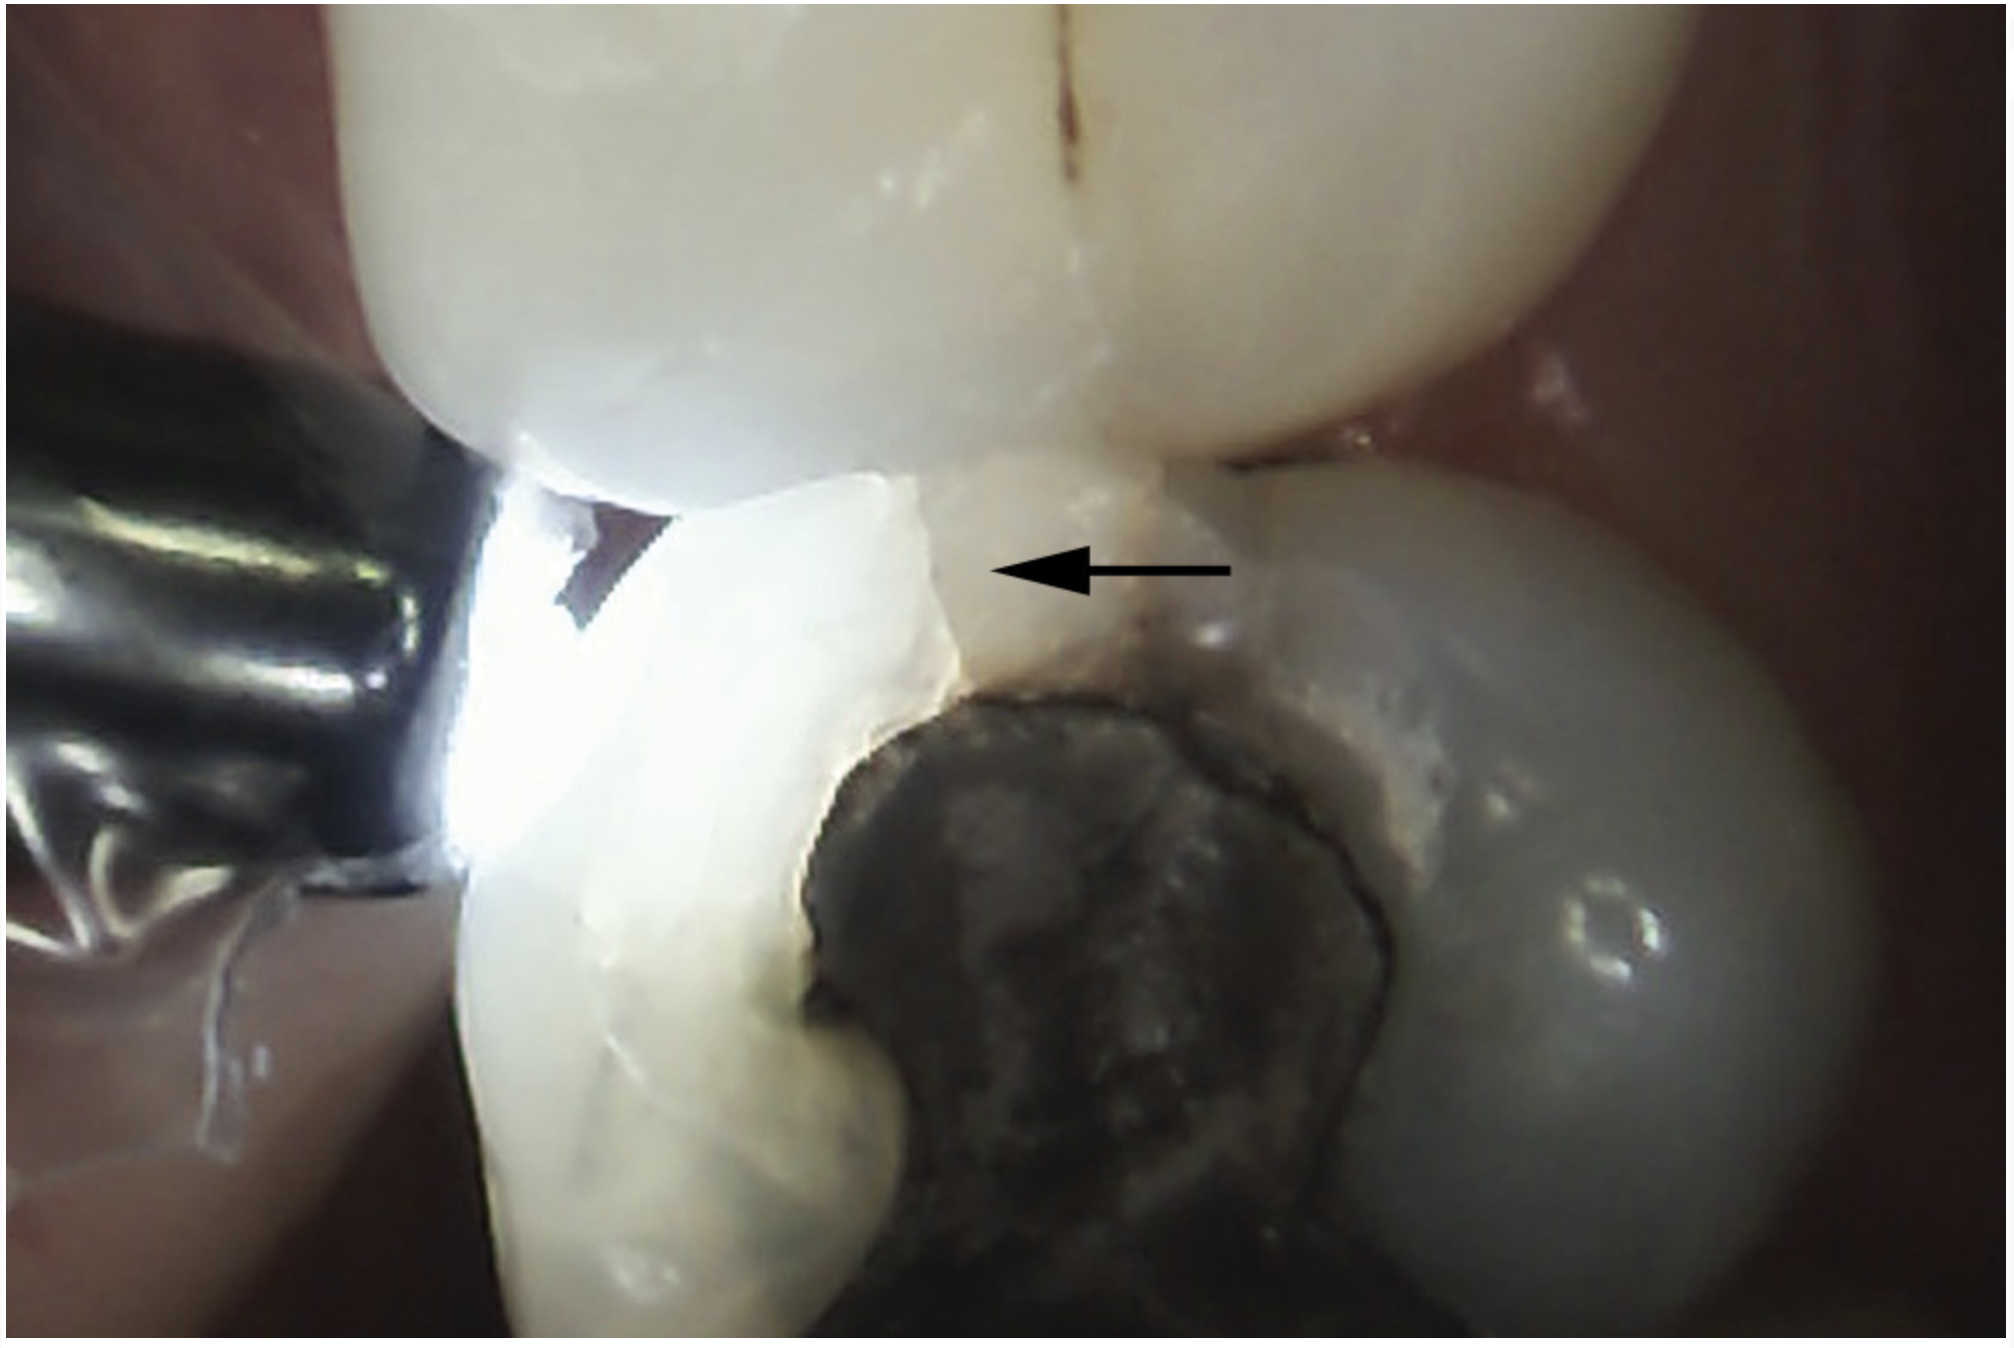

The detrimental effects of vertical cracks on the dentition and surrounding tissues stem mostly from bacterial invasion into the microscopic space of the crack, as well as physical irritation and liquid microleakage, even though the separation of the segments may not be clinically visible.3,5-7 As bacteria penetrate cracks, they invade underlying structures, such as the coronal dentin, pulp, root structure, and periodontal tissues, leading to varying degrees of pathologies. Enamel cracks have been found to provide caries-producing bacteria access to the dentin-enamel junction, leading to caries inside the tooth without any externally visible evidence (Figure 1).5 Dentin cracks are pathways of bacteria to the dentinal tubules and pulp, leading to various pulpal pathologies, including reversible and irreversible pulpitis and pulp necrosis.6,8

Fig 1. Decalcification in enamel along a crack line (arrow) and caries at the dentin-enamel junction of a mandibular left first molar (disto-occlusal view).

Figure 1